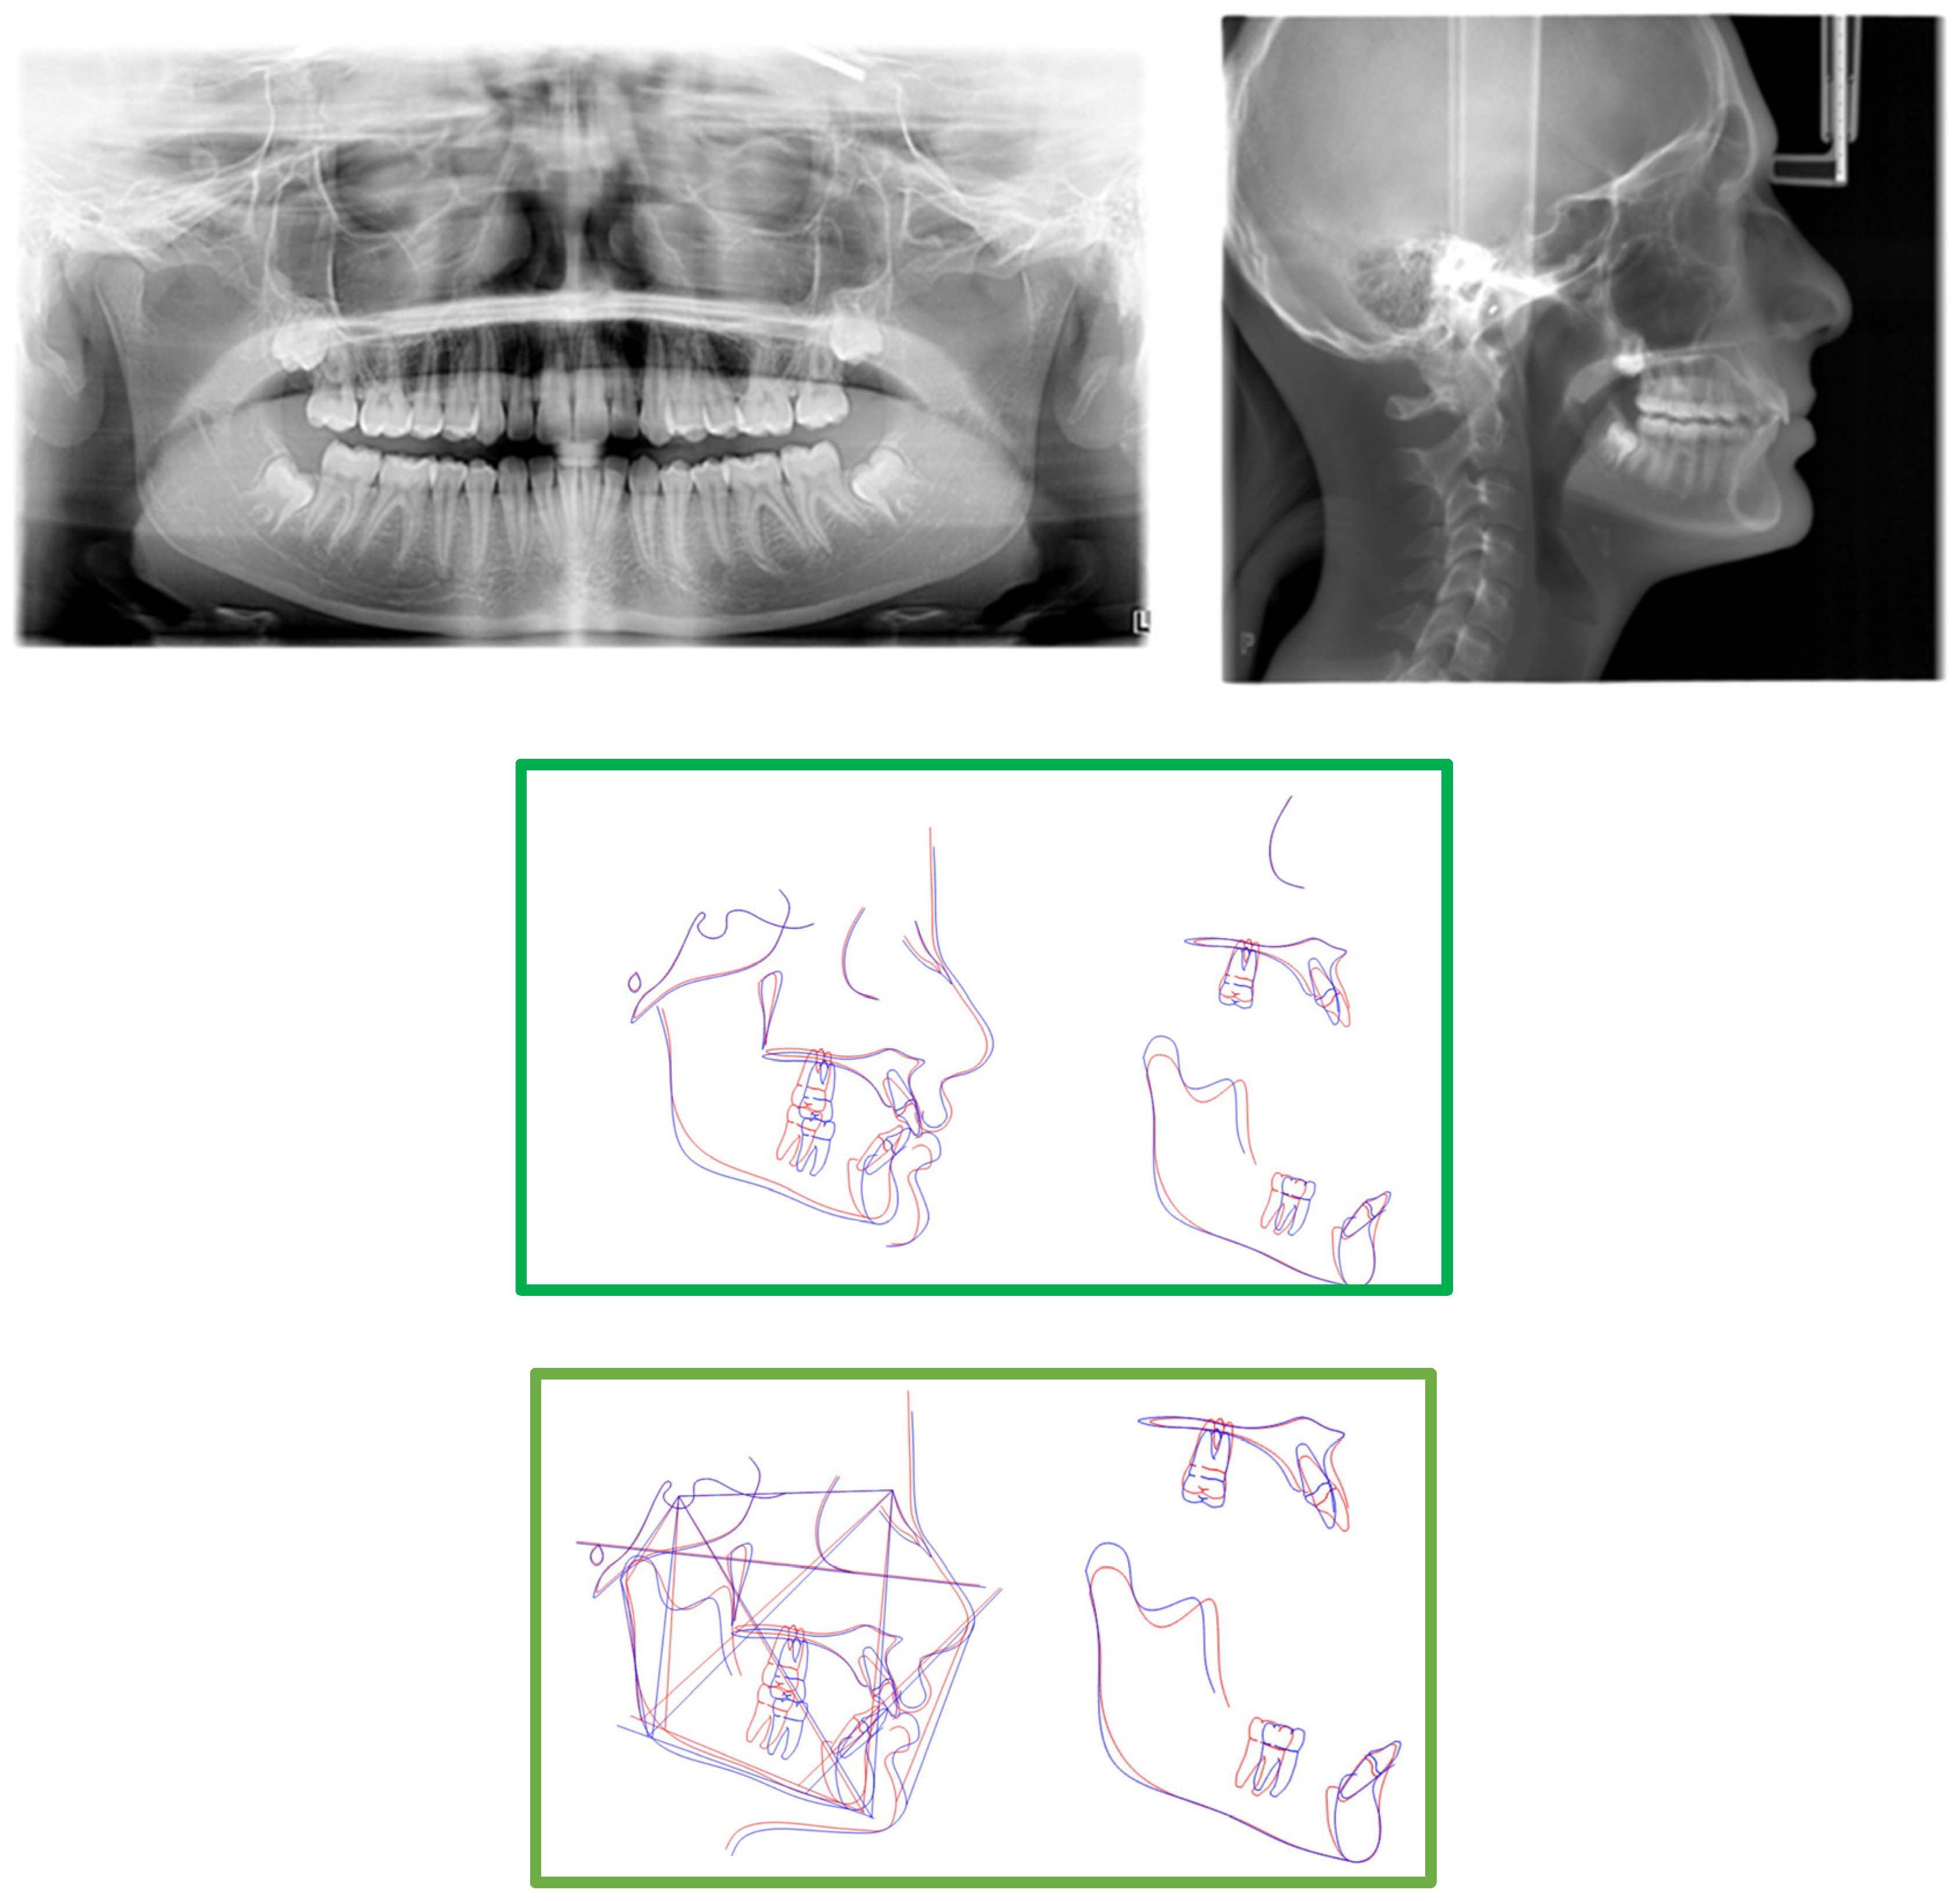

2. Presentation of Case Report

2.3. Treatment Progress

- Surgical exposure of the left mandibular canine using a diode laser (Doctor Smile, Lambda Spa, Brendola, Vi, Italy) for operculectomy and excision of fibromucous tissue. The corticotomy was performed using an ultrasonic piezosurgery system (Mectron Medical Technology, Carasco, Genova, Italy). A bottom (3M Unitek, Monrovia, CA, USA) was placed labially as close as possible to the canine’s coronal tip, combined with a metallic ligature and a cantilever (0.016 × 0.022 TMA, American Orthodontics, Sheboygan, WI, USA) without sutures (Figure 3a,b). The cantilever allowed for distal and buccal traction with light forces (1.7–2.8 ounces). A lingual arch was soldered (passive only on 31–32);

- Fixed multibrackets appliance (American Orthodontics Corp., Sheboygan, WI, USA, MBT prescription) were placed in the upper arch with 0.014 NiTi wire, bent back for controlling anchorage;

- After one month, a 0.016 NiTi wire was inserted in the upper arch;

- Fixed multibracket appliances were placed in the lower arch with a 0.014 NiTi wire, starting vertical traction of the canine. A bent back was used for controlling anchorage;

- After two months, the inferior left canine achieved a vertical position and reached its position in the arch. The bracket was replaced to adjust its axial inclination, and then a 0.016 NiTi wire was inserted;

- Before using stainless steel wire, a ligature from 16 to 26 and 36 to 46 for controlling anchorage was placed;

- 0.016 × 0.022 stainless steel wire was inserted in the upper and lower arches;

- 0.019 × 0.025 stainless steel wire was inserted in the upper and lower arches;

- Reverse Pin System” was placed on 13 and 23 to initiate class II biomechanics. Class II elastics (upper canines and first inferior molars) 3/8 4.5 ounces were used (Figure 3c). Class II elastics were used for 18 h every day;

- One year later, class I occlusion was achieved, and the class II elastics were used only during nighttime;

- Two years later, the appliance was deboned, and positioner retainers were given to the patient with the prescription to wear them every night.